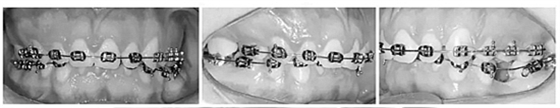

4.影像檢查:右上前磨牙和左下第二前磨牙缺失(Figure 4)。在另一名牙齒矯正醫(yī)師治療4年后,患者在19歲時被轉(zhuǎn)診給我們。他的咬合特征與他的初始狀態(tài)非常相似(Figure 5)